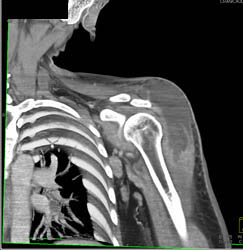

Diagnosis

Pectus